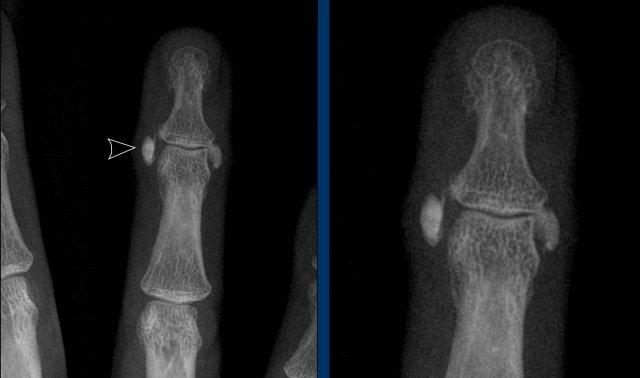

Viêm màng xương trong viêm khớp vảy nến

Đây là bệnh nhân viêm khớp vảy nến.

Lưu ý hình ảnh viêm màng xương mờ nhạt tại đốt ngón xa của ngón 1 bên phải (đầu mũi tên).

Có các bào mòn xương nhỏ tại chỏm đốt ngón xa của ngón 2 và 3 bên trái (mũi tên trắng).